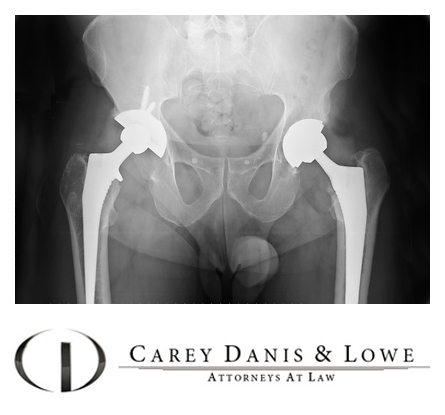

Примеры протезов коленных суставов Zimmer

Раздел: Образы вокруг